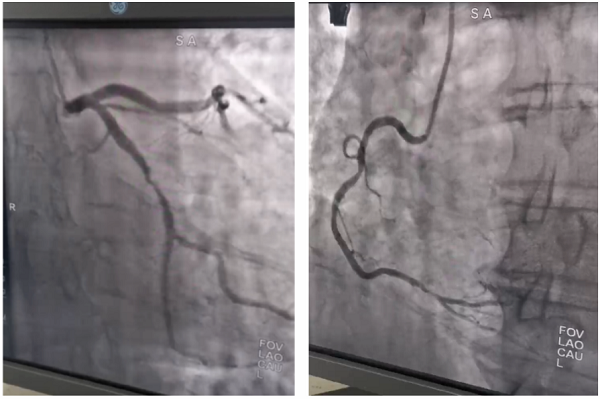

病例:患者男性,67岁,诊断“脑梗死、高血压、糖尿病、冠心病”,颈动脉彩超提示左侧颈动脉起始段狭窄,为进一步明确脑血管情况,预行脑血管造影;患者同时合并冠心病,提出希望能在脑血管造影同时,同台行冠脉造影明确心脏血管情况;为满足患者需求,我院神经内科立即请心血管内科医师会诊评估,最后决定为患者同台行冠脉及脑血管造影,造影顺利完成,精准评估了患者心脑血管狭窄程度,制定后期治疗计划,造影耗时约1.5小时,患者及家属非常满意。

心脏与脑血管造影手术是一种先进的影像学检查技术,通过向血管内注入造影剂,使心脏和脑血管显影,从而动态清晰地显示血管的形态、结构和血流情况。这种技术对于诊断血管狭窄、阻塞、动脉瘤等病变具有重要意义,并为后续的治疗提供精确的指导。

冠脉支架治疗